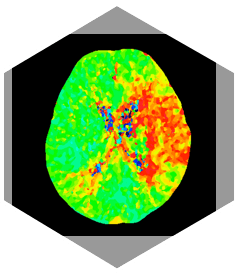

• Iterativer Dosisreduktionsalgorithmus (iDREAM)